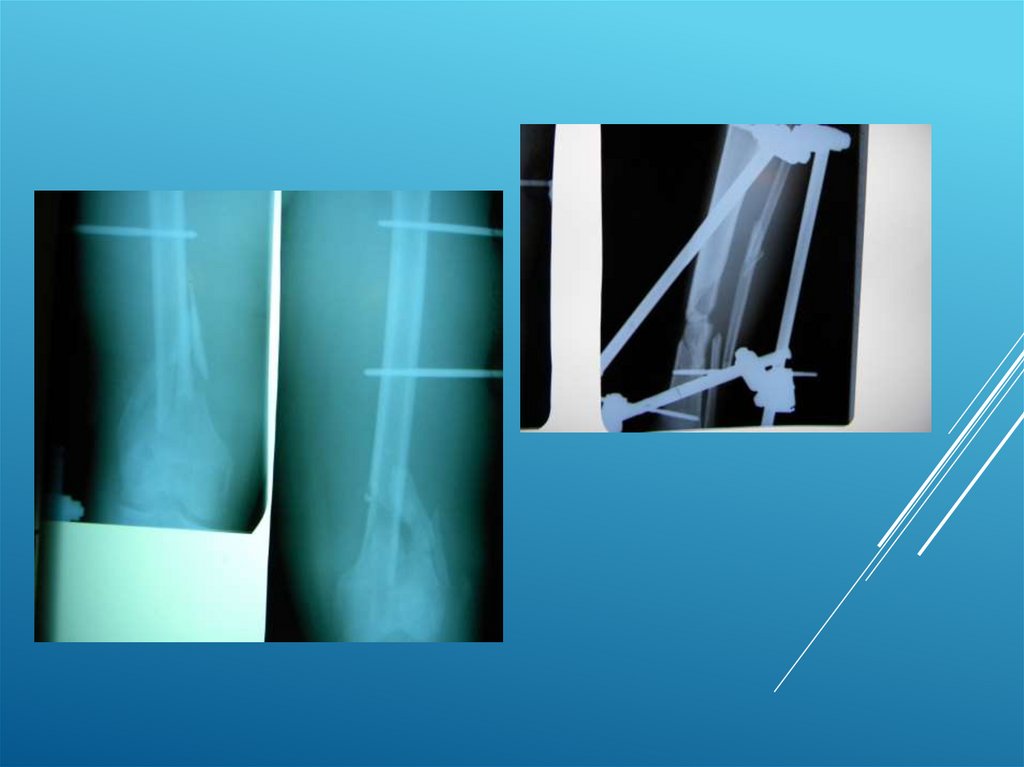

Пациентка К. 54 года

14.

15.

Пациент А. 50 лет

16.

17.

18.

19.

20.